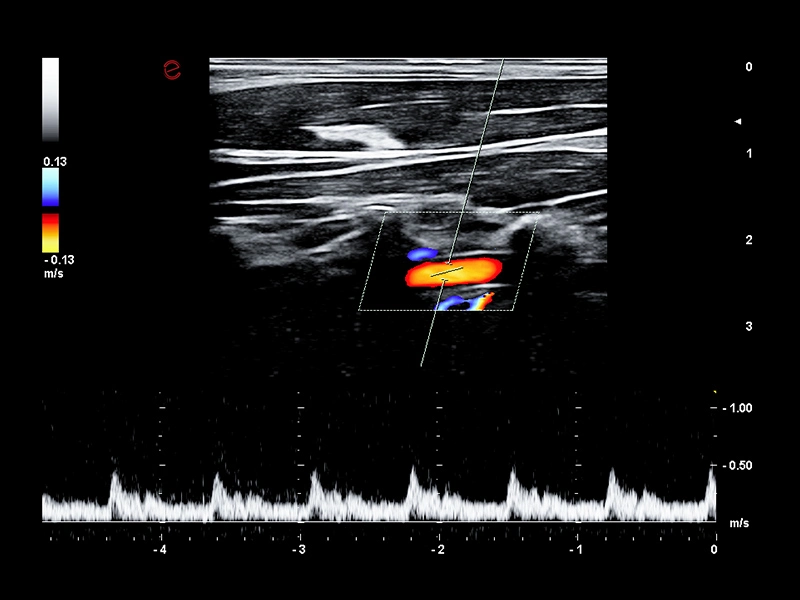

MyLab™9 Platform - Ultra-sensitivity Colour Doppler in detection vertebral artery

MyLab™9 Platform - Ultra-sensitivity Colour Doppler in detection vertebral artery